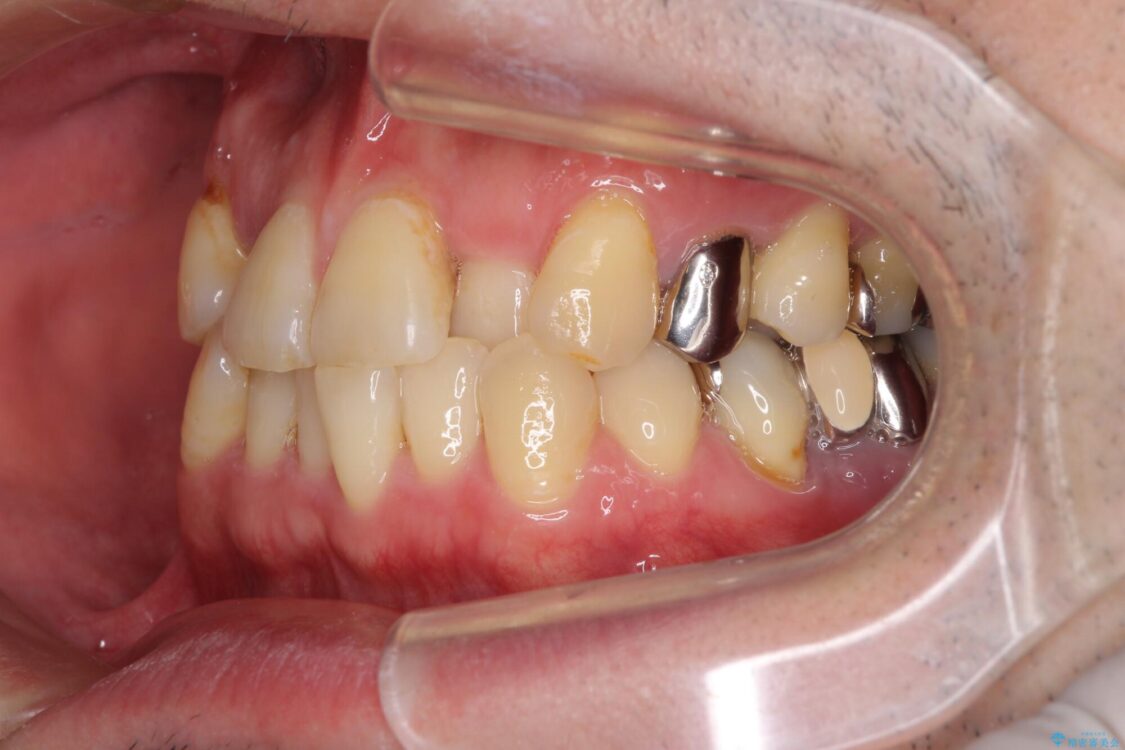

奥歯の痛みと前歯のデコボコを気にして来院された患者様です。

左右下顎の大臼歯は、ともに歯根が破折しており、抜歯が必要な状態でした。

放置したことで炎症による骨吸収が顕著であるため、骨造成を併用してインプラント埋入を行うこととしました。

咬み合わせは受け口傾向であり、上顎前歯の叢生が顕著であったことから、第1小臼歯抜歯による矯正治療も検討しましたが、下顎大臼歯を左右ともに抜歯するため、非抜歯による矯正治療を行うこととしました。

治療前